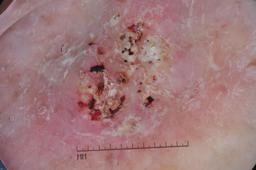

ISIC-DICM-17K (ISIC Dermoscopic Images and Clinical Metadata 17K) is a curated and balanced dataset derived from the International Skin Imaging Collaboration (ISIC) Archive Gallery. It comprises 17,060 dermoscopic images and clinical metadata (8,530 melanoma and 8,530 non-melanoma classes).

For more details, please follow the project’s GitHub repository: https://github.com/mmu-dermatology-research/isic-dicm-17k

This dataset was used in this study and benchmark to explore the effectiveness of multimodal learning for skin lesion classification:

S. Ahammed, X. Cui, W. Lu and M. H. Yap, "Skin Lesion Classification using Dermoscopic Images and Clinical Metadata: Insights from Multimodal Models," 2025 IEEE/CVF Conference on Computer Vision and Pattern Recognition Workshops (CVPRW), Nashville, TN, USA, 2025, pp. 222-230, DOI: 10.1109/CVPRW67362.2025.00027